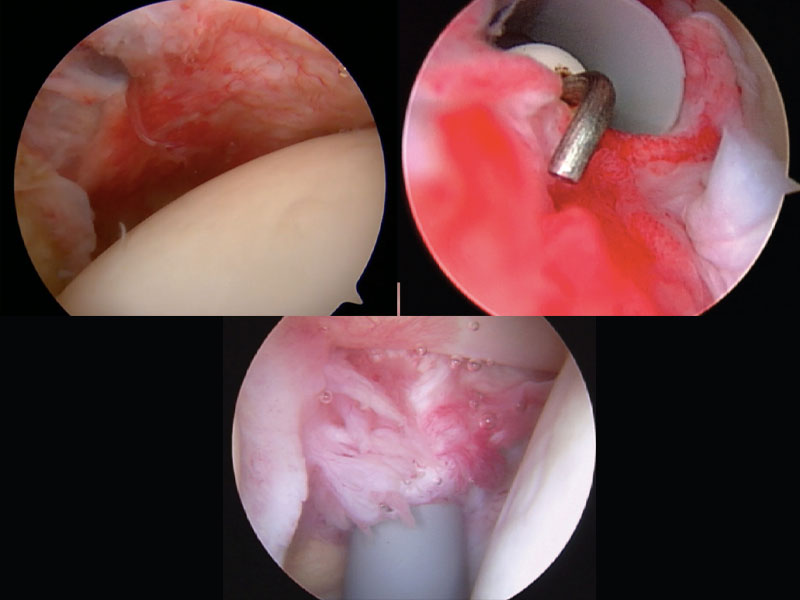

Como a doença apresenta uma resolução espontânea, o tratamento cirúrgico só é empregado quando os sintomas, principalmente de limitação dos movimentos é muito importante, e traz limitações severas para as atividades dos pacientes. É raro que seja necessário realizar o tratamento cirúrgico, mas pode ser realizado por uma artroscopia.